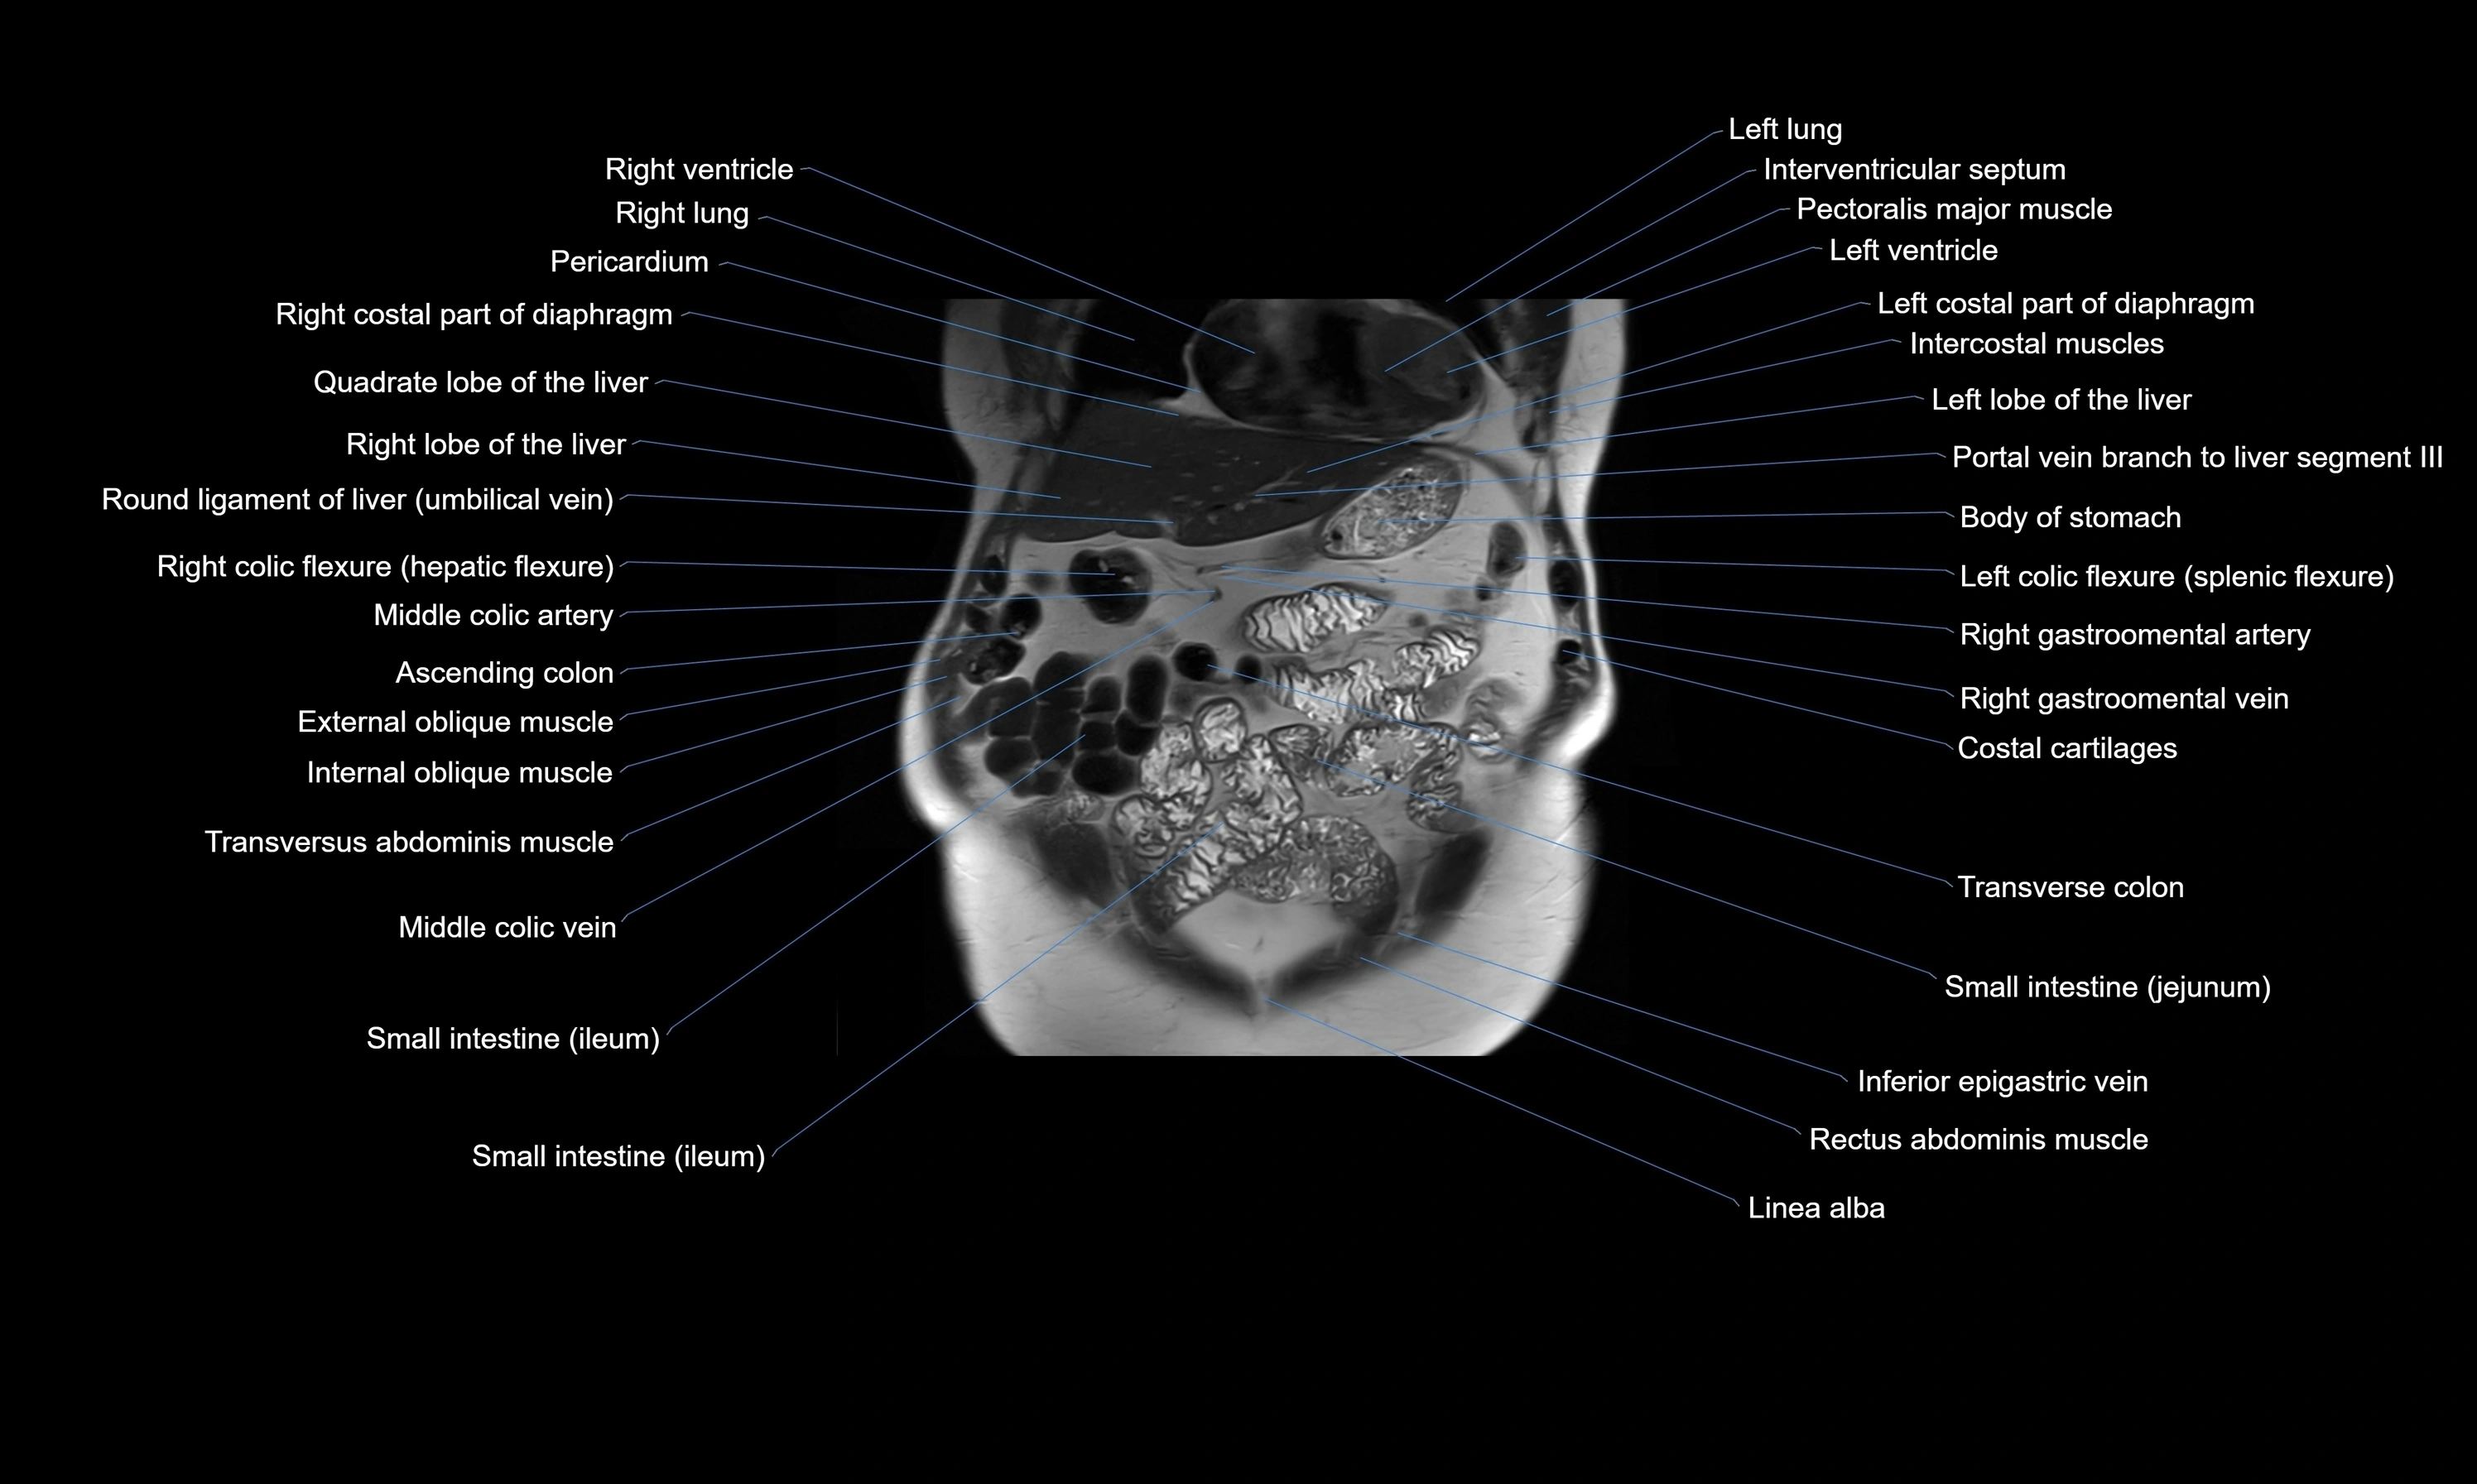

MRI images